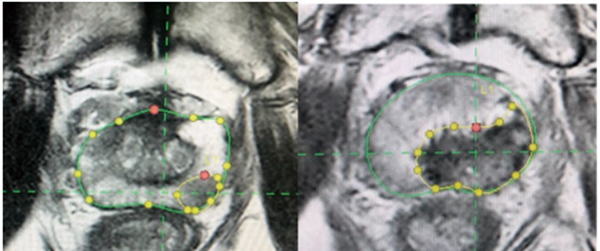

研究人员在该项Ⅱ期试验(PFLT-PC)中招募了100例前列腺特异性抗原(PSA)水平<15 ng/mL的、<T2c期的、国际泌尿病理学会(ISUP)分级分组为2~3的、多参数MRI有可见病灶的、局限性前列腺癌男性患者,在日间病房全身麻醉下给予ProFocal前列腺组织消融激光疗法的冷激光聚焦治疗(Medlogical Innovations)。

主要终点包括72小时内多参数MRI组织消融的充分性,以及治疗后3个月的活检情况。

结果显示,患者的中位年龄为66岁(IQR:60~72岁),中位PSA水平为5.9 ng/mL(IQR:3.9~7.6 ng/mL),中位前列腺体积为39 mL(IQR:30~51 mL),中位MRI病灶体积为0.84 mL(IQR:0.57~1.2 mL),中位治疗时间为60 min(IQR:47~70 min)。